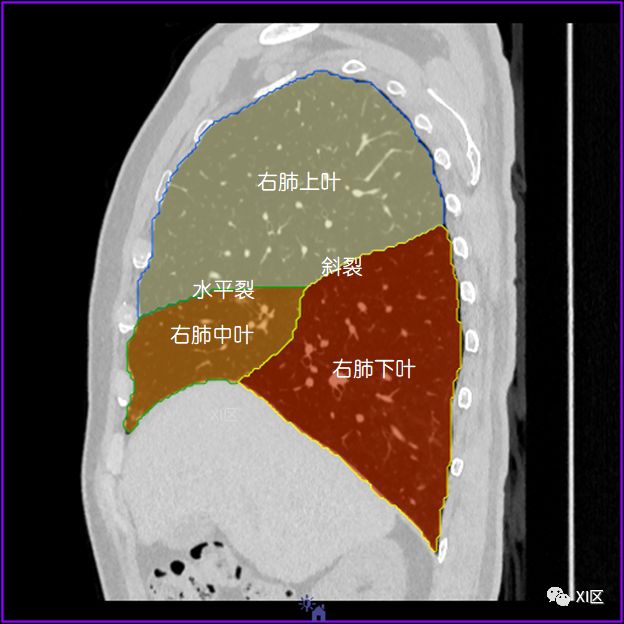

左肺借斜裂成上、下两叶;右肺借斜裂和水平裂成上、中和下叶三叶。

矢状位

肺表面重建显示叶间裂和肺的分叶

透视图显示肺的叶间裂和肺的分叶